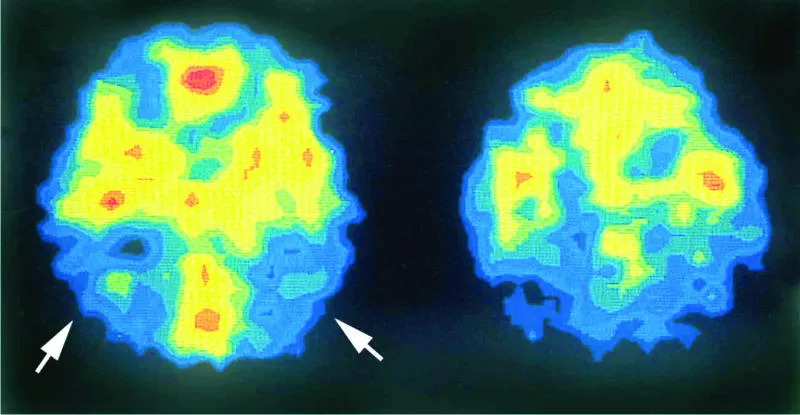

وأظهرت الدراسة التي نشرت في مجلة علوم طب الحركة أن الفئران المصابة بمرض بريون تعرضت لمشاكل حادة في الذاكرة والحركة، وماتت في غضون 12 أسبوعا.

ومع ذلك، لم تظهر الفئران التي أعطيت هذا المركب الكيميائي أي علامة من علامات فقدان أنسجة الدماغ.